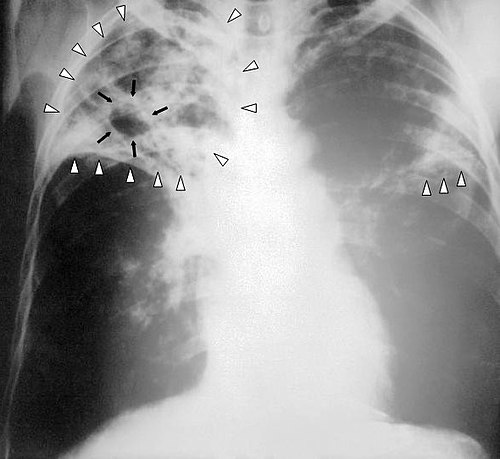

patient avec une tuberculose pulmonaire avancée

Publié par : nacer jardani mahmoud